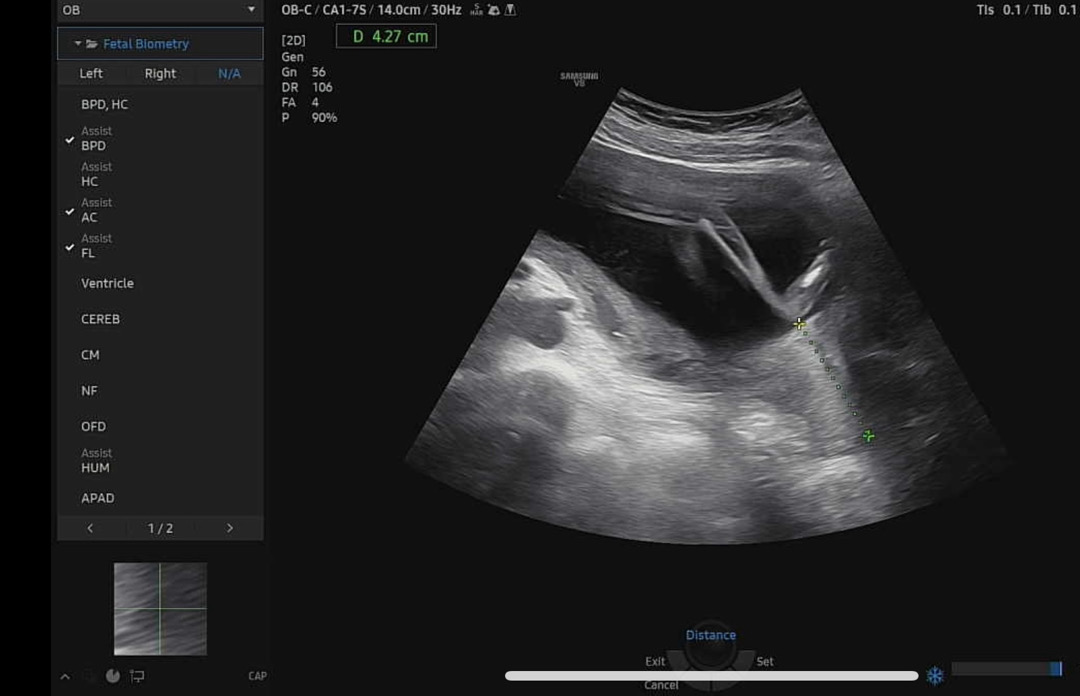

저건 무슨길이 잰거일까요?

자궁길이 잰거같아요~!

저도 이렇게 쟀을때 자궁경부길이 라고 하시더라구여!